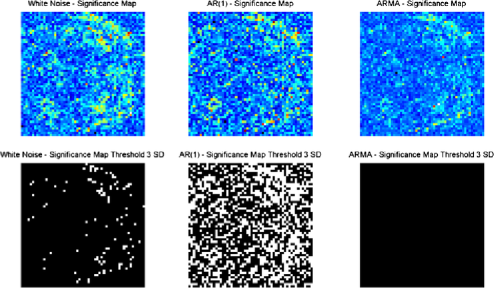

Resting state data is inherently different from activation data and the model for the noise will be inherently more important in this case, in that no activation is expected to take place. As can be seen in Figure 10, depending on whether a white noise, AR(1) or ARMA()

model is chosen, the number of change-points within the image varies considerably, despite the same threshold being applied. The same analysis using the methodology proposed in this paper resulted in nonstationarities being detected (see Figure 3). The differences in the EWMA analysis for alternative noise models are likely due to the difficulty in expressing the noise structure accurately for resting state data, in comparison to activation-baseline tasks where AR(1) and ARMA() type noise structures are known to be fairly good approximations.